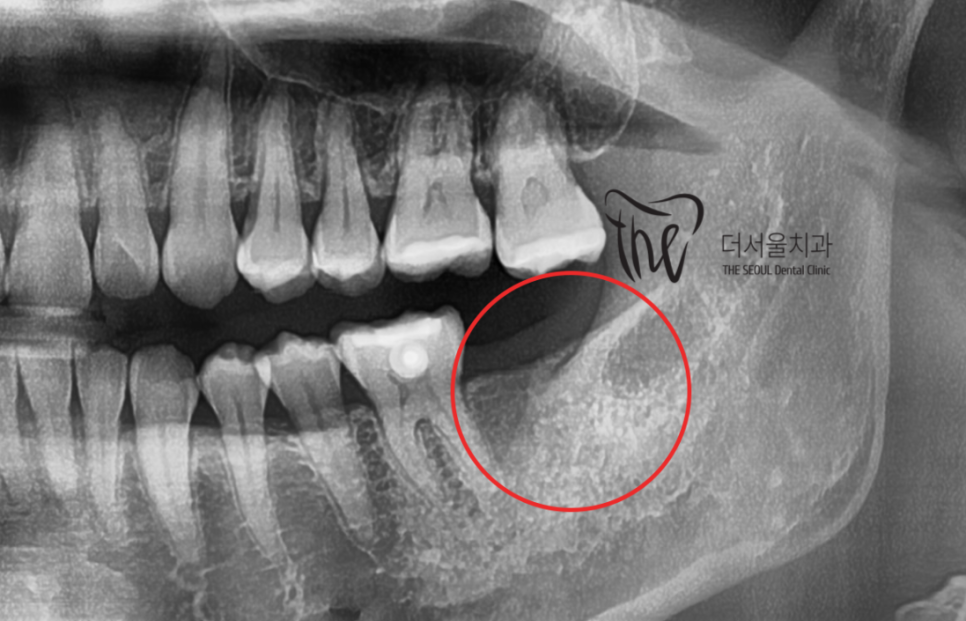

다만 하나 아쉬운 점은,

사랑니의 맹출 위치 불량에 따라서

바로 앞에 있는 제2 대구치는 발치 결정을

내리게 되었습니다.

이미, 치축이 상당히 쓰러져 있는 상황이며

업라이팅을 해드리기에는 시간이 오래 걸릴뿐더러

예후 또한 좋지 않을것으로 판단이 되어서

부정교합 2급 치료가 다 끝나는 시점에 맞춰서,

임플란트로 대체를 해드리기로 했죠.